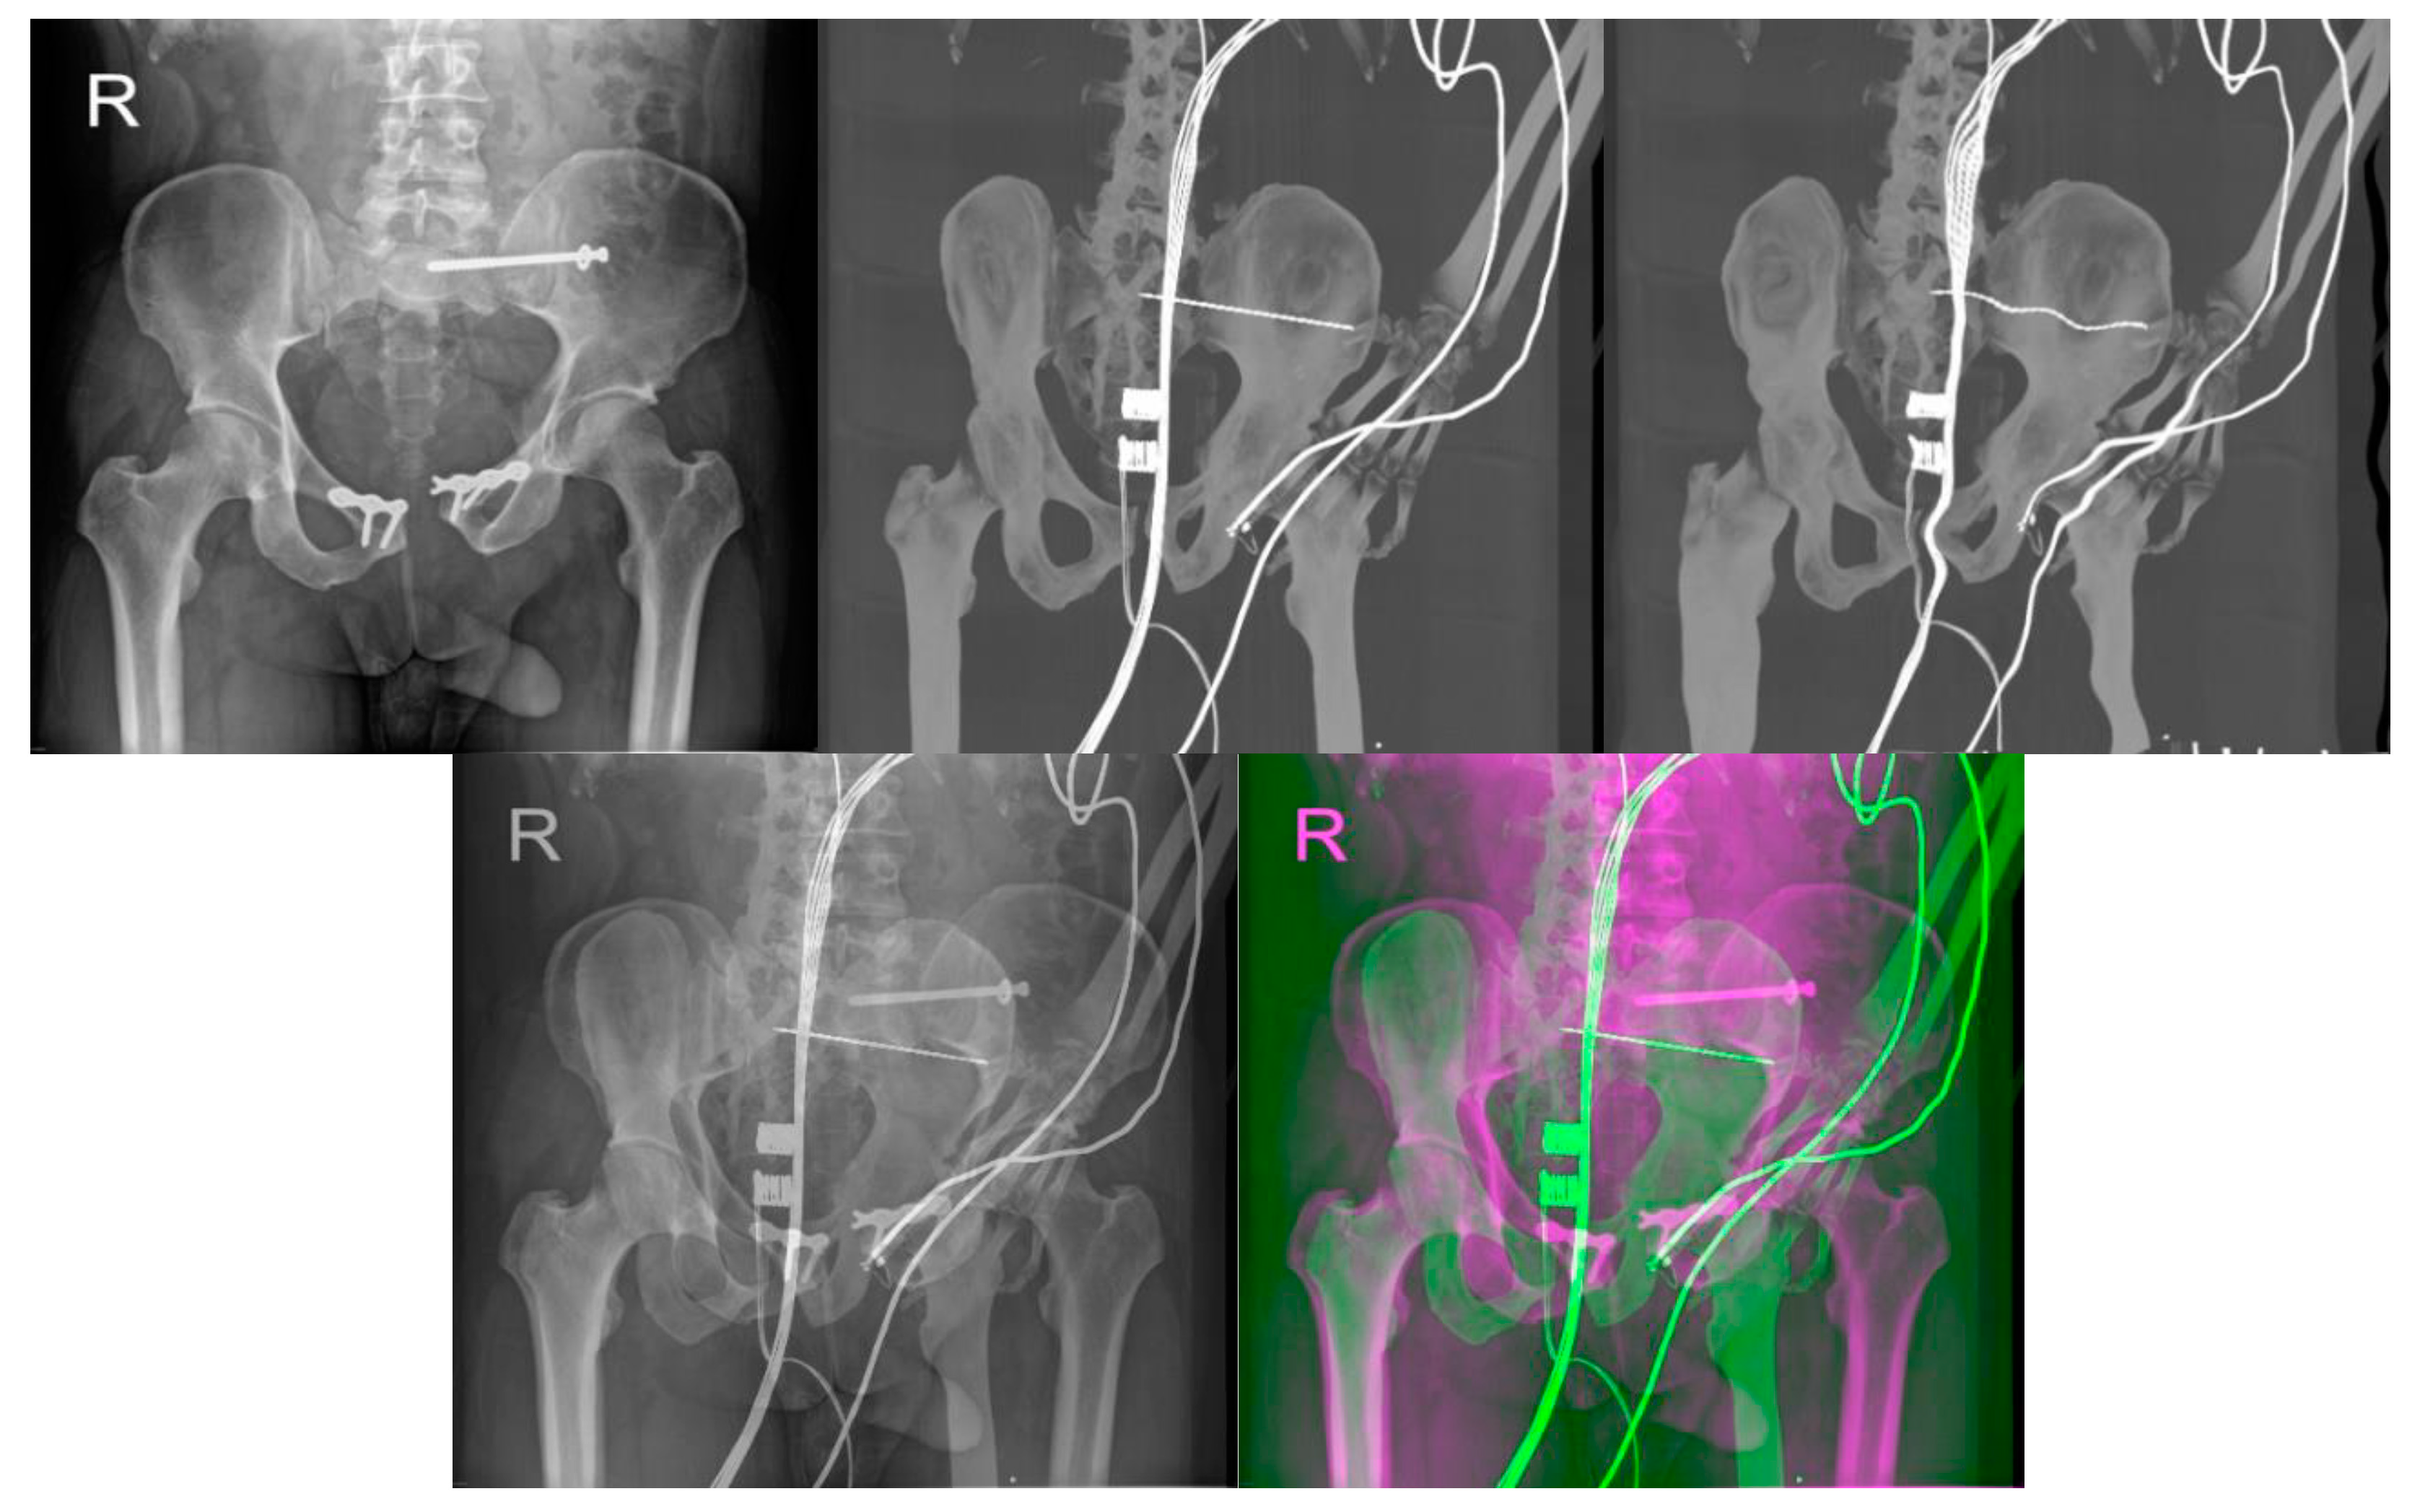

- Reconstructed DDR projections with virtual iliosacral screw

- Multimodal (X-ray/CT) image registration for optimal CT slice selection according to the reference X-ray image.

- Multimodal image registration of DRR projections to a reference X-ray image